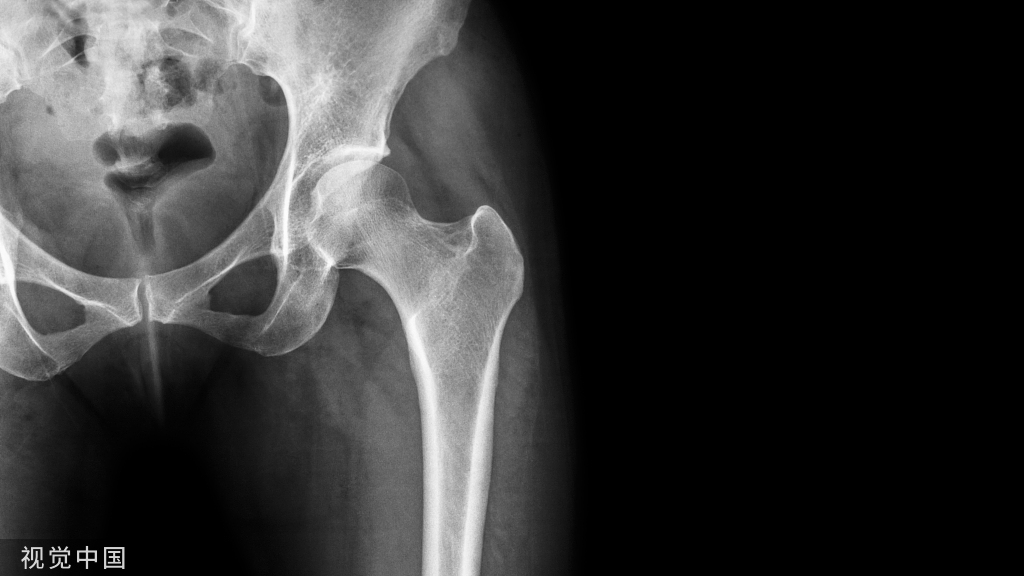

尺神经从肱骨内上髁至尺侧腕屈肌出口的这段通道被称为肘管,其底为肘内侧韧带,顶为尺侧腕屈肌,尺侧腕屈肌两个头之间为腱膜组织。迟发性尺神经炎多是因尺神经肘管段的慢性损伤引起,所以也称作肘管综合征。

早期尺神经充血水肿、神经鞘膜增厚,继之出现缺血、神经纤维细胞浸润、纤维变性、粘连、纤维化。